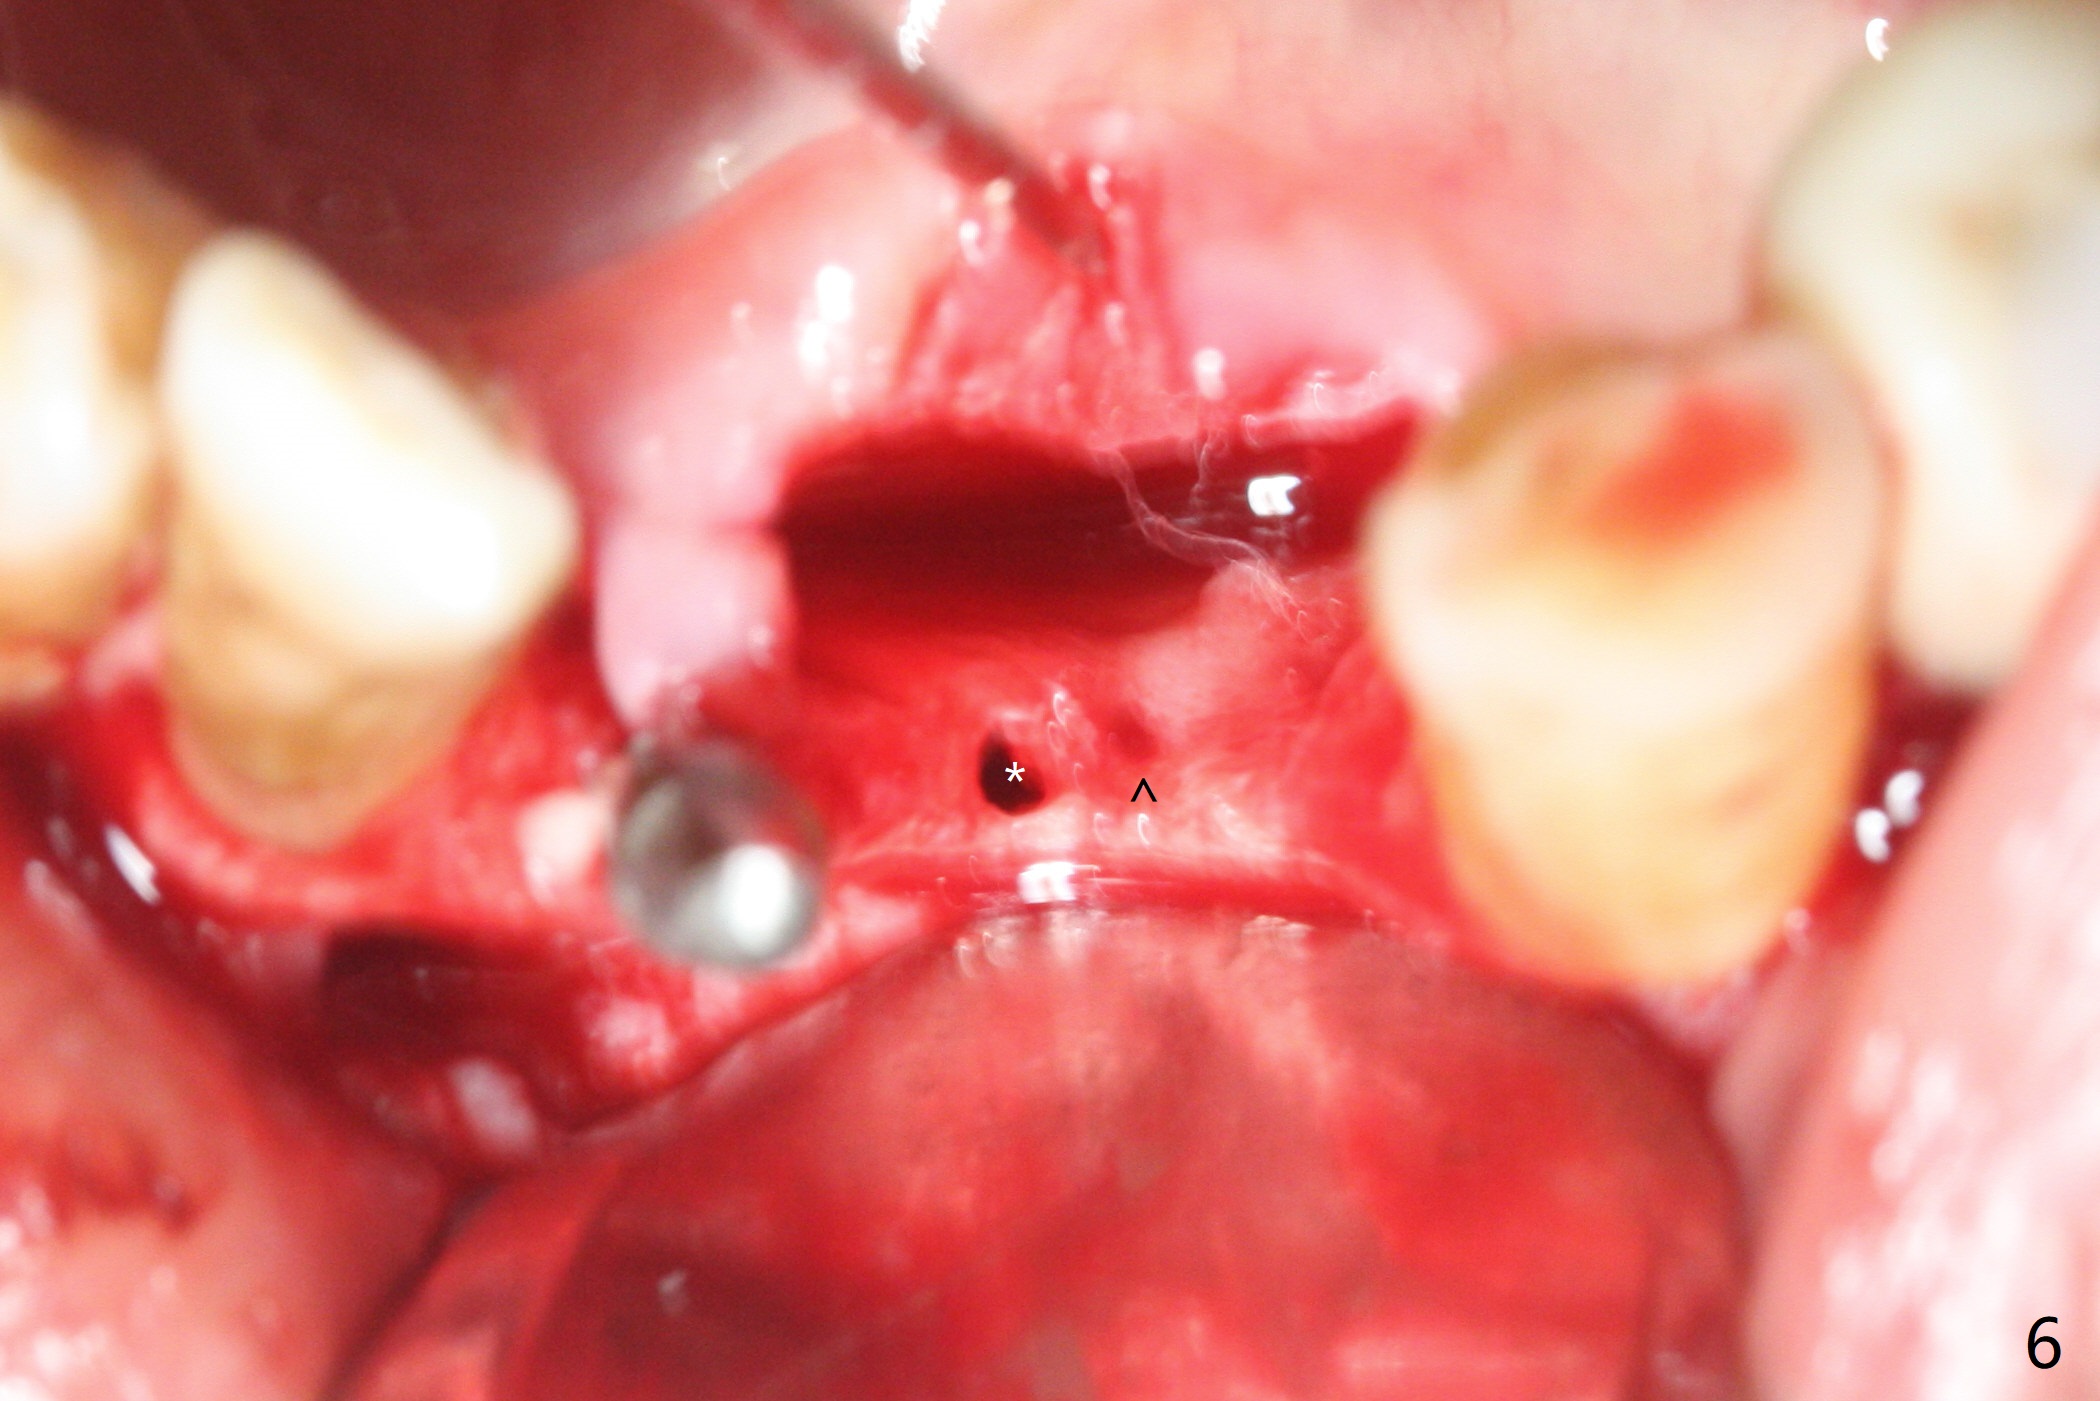

Two and a half months after loss of a 2 mm 1-piece approximately at #23 (Fig.1,2), it appears that the site of #24 (Fig.3 line) is more appropriate because the bone is higher. After removal of the pointed ridge top, osteotomy is initiated with 1.2 mm drill, followed by 1.5 mm one (Fig.4,5). When the 1.5 mm drill is removed, the new osteotomy (Fig.6 *) is mesial to the old one (^). Since the ridge is narrow (Fig.5,6), a 2x14(4) mm 1-piece implant is placed with GBR (Fig.7). Due to overprep, the torque is 20 Ncm. No immediate provisional is fabricated. Instead periodontal dressing is applied around these 2 implants. Two separate provisionals are fabricated when the wound heals. The one at #24 does not stay. The implant at #24 appears to osteointegrate 6.5 months postop (Fig.8). When the crowns are cemented, the margin is supragingival (Fig.9,10). Water Pik is recommended.